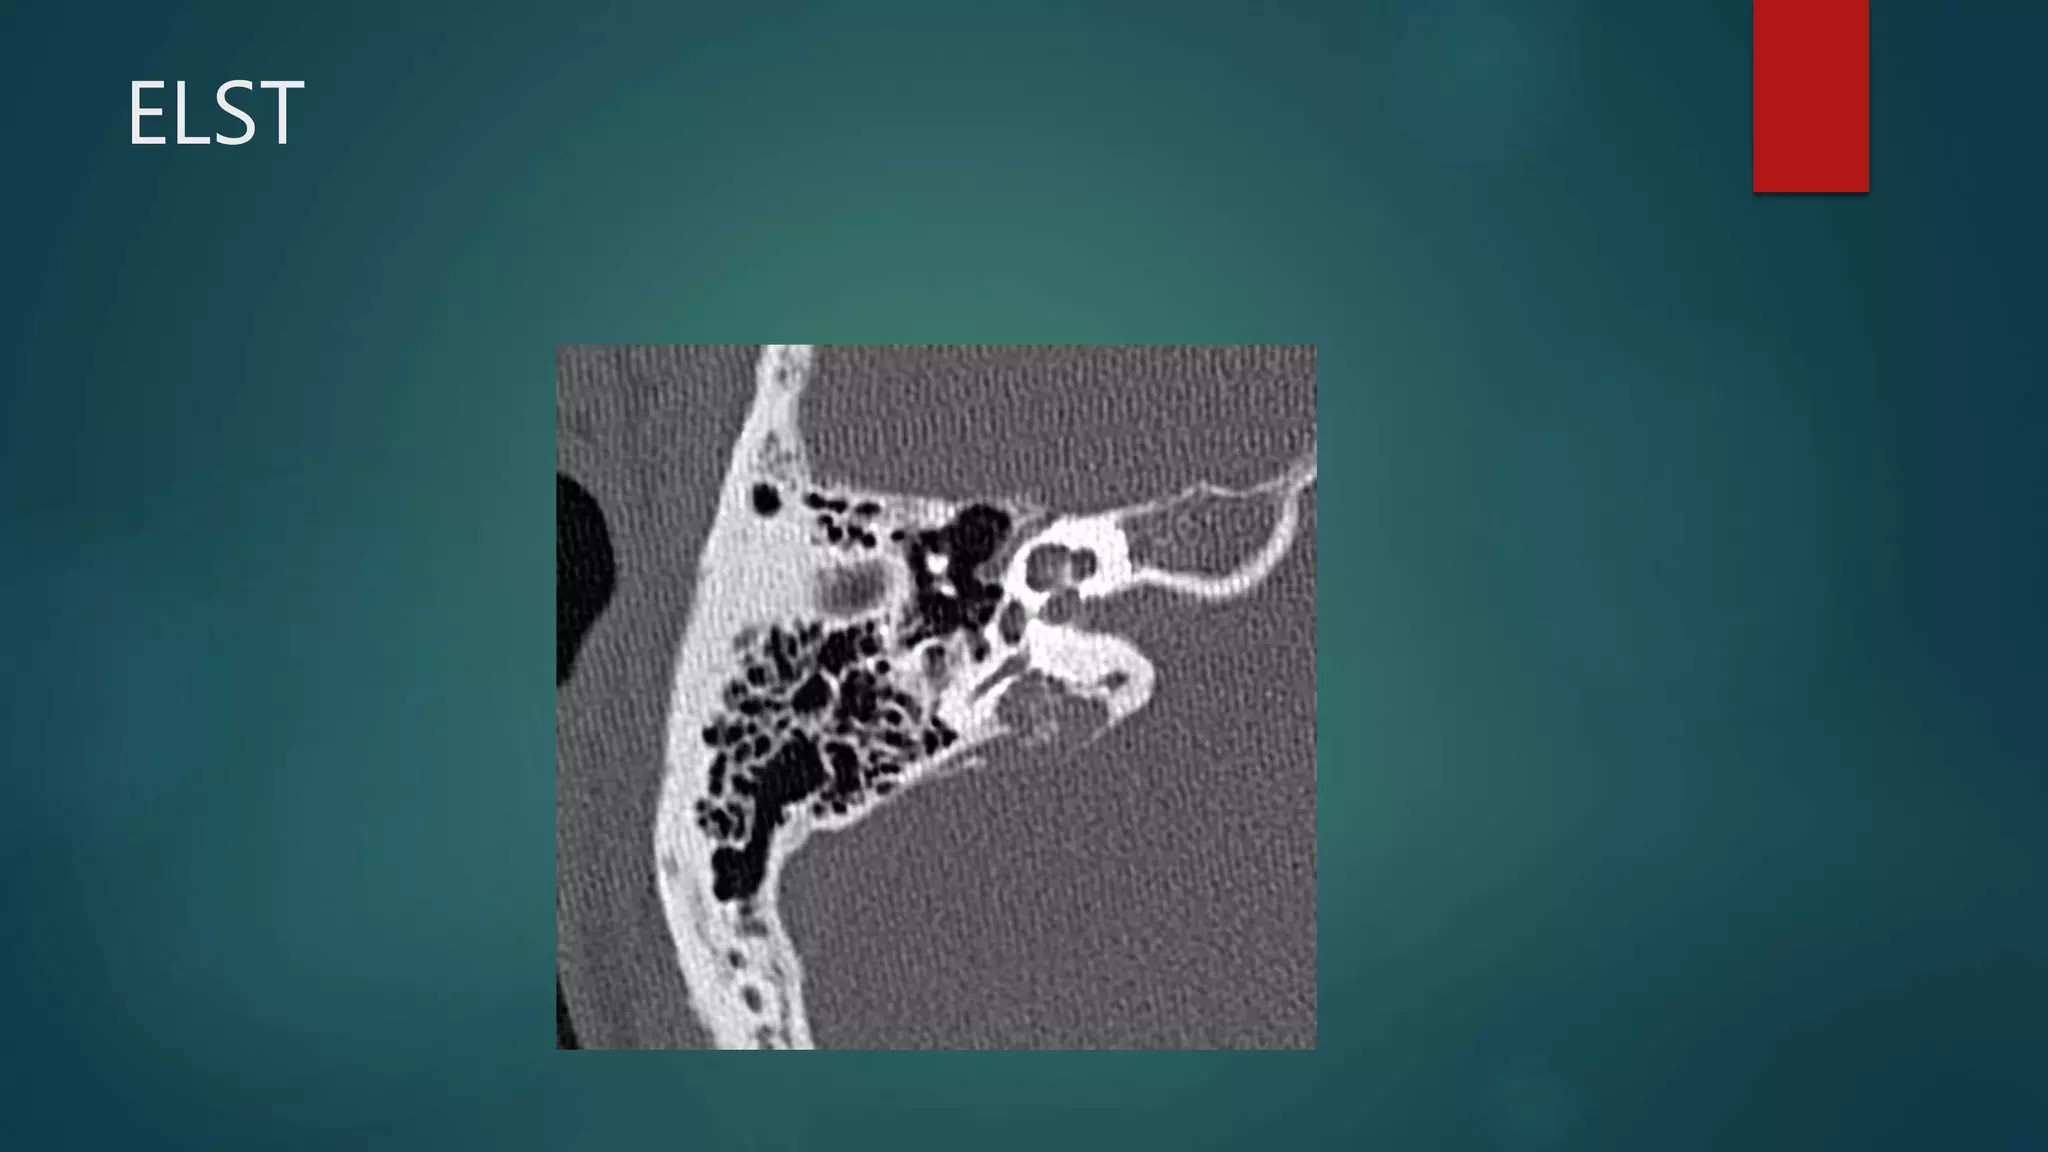

ELST

• E: eye dysfunction (retinal haemangioblastoma), endolymphatic sac

tumours